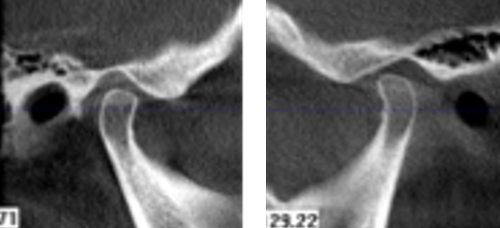

· 颞下颌关节:无肌肉压痛,张口偏斜等阳性体征。

· 双侧髁突骨皮质连续。

· 修复体戴入后髁突位于关节窝内的适中位置。

· X线片显示,种植体周骨稳定性、关节髁突位置评估均无异常。